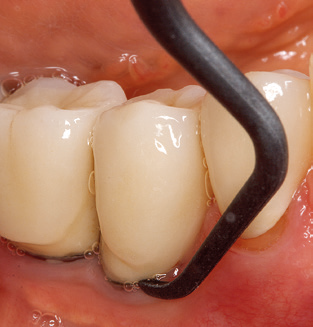

Die gute Ausleuchtung des Arbeitsfeldes stellt eine wesentliche Erleichterung dar. Bei dem von den Autoren genutzten System ist dies gelungen, indem ein 5­facher LED­Ring in das Handstück integriert wurde. Natürlich werden für dieses System unterschiedliche Arbeitsspitzen für die jeweiligen Indikationsbereiche angeboten. Eine gerade, universell einsetzbare Spitze ist das Basisinstrument zur maschinellen Instrumentierung natürlicher Zähne (Abb. 5a und b). Für schwer zugängliche Bereiche im Seitenzahnbereich werden gebogene Spitzen angeboten, die auch einen Zugang zu freiliegenden Furkationen ermöglichen (Abb. 6).

Abb. 4: Für das Sondieren an dentalen Implantaten sind biegsame, millimeterskalierte Sonden empfehlenswert (z.B. Colorvue Kit PCV11KIT6, Hu-Friedy). – Abb. 5a und b: Eine gerade Arbeitsspitze (1P, W&H Dentalwerk Bürmoos GmbH) ist universell für die Instrumentierung natürlicher Zähne geeignet. – Abb. 6: Für die Bearbeitung schwer zugänglicher Bereiche der Zahn- und Wurzeloberflächen (z.B. Furkationen) bieten sich gebogene Arbeitsspitzen (3Pr/3Pl, W&H Dentalwerk Bürmoos GmbH) an. – Abb. 7: Die spitz zulaufende sechseckige Implantatreinigungsspitze (1I, W&H Dentalwerk Bürmoos GmbH) ermöglicht eine atraumatische und effiziente Reinigung der Kronen- und Abutmentoberflächen. – Abb. 8: Für die manuelle Instrumentierung der Implantatoberflächen sind Titan- oder Carbonküretten geeignet.